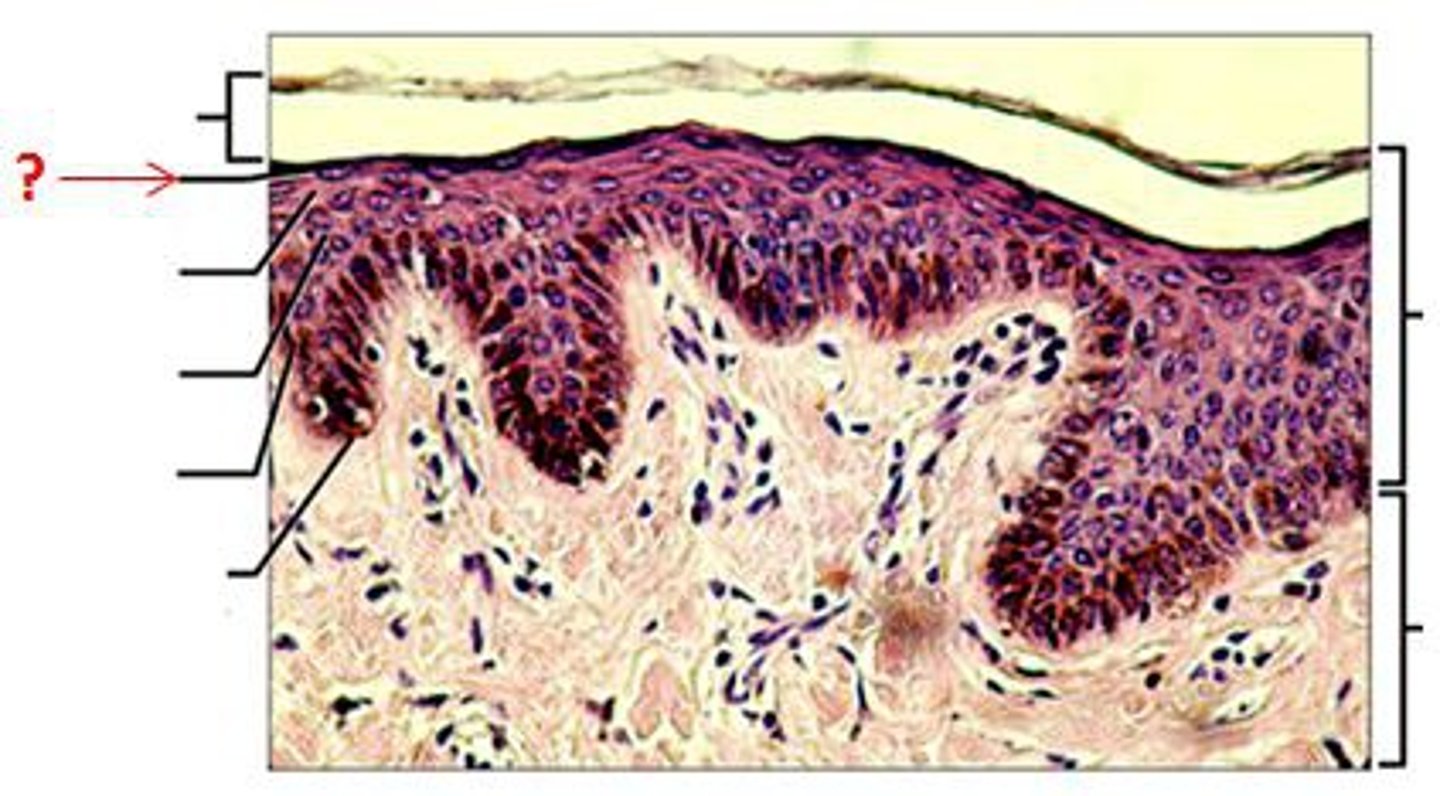

Epidermis

Outer layer of skin

stratum corneum

outermost layer of epidermis

stratum lucidum

Clear, transparent layer of the epidermis under the stratum corneum.

stratum granulosum

a layer of the epidermis that marks the transition between the deeper, metabolically active strata and the dead cells of the more superficial strata

stratum spinosum

stratum basale

the deepest layer of the epidermis consisting of stem cells capable of undergoing cell division to form new cells

Dermis

Inner layer of skin

papillary layer

outer layer of the dermis, directly beneath the epidermis; made of loose connective tissue

reticular layer

The deeper layer of the dermis that supplies the skin with oxygen and nutrients; made of dense irregular connective tissue

dermal papillae

a fingerlike projection of the dermis that may contain blood capillaries or Meissner corpuscles (of touch)